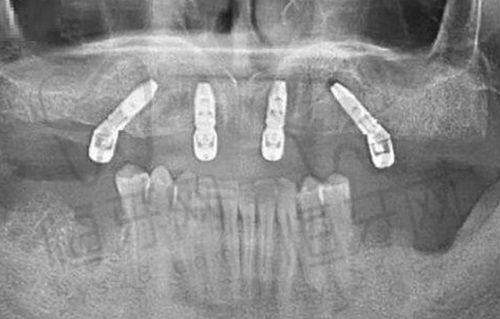

邵阳雅贝康口腔医院在种牙技术上那是紧跟潮流,数字化种植(3D导板精细定位)技术就像给种牙手术装了“导航系统”,让种植更加精细。还有瑞士ITI/瑞典诺贝尔等高端植体可选,满足不同患者的需求。

特色亮点:数字化种植技术精细度高,能大大提高种牙的成功几率。医生团队专研复杂病例,再难的种牙问题在这里都能找到解决方案。